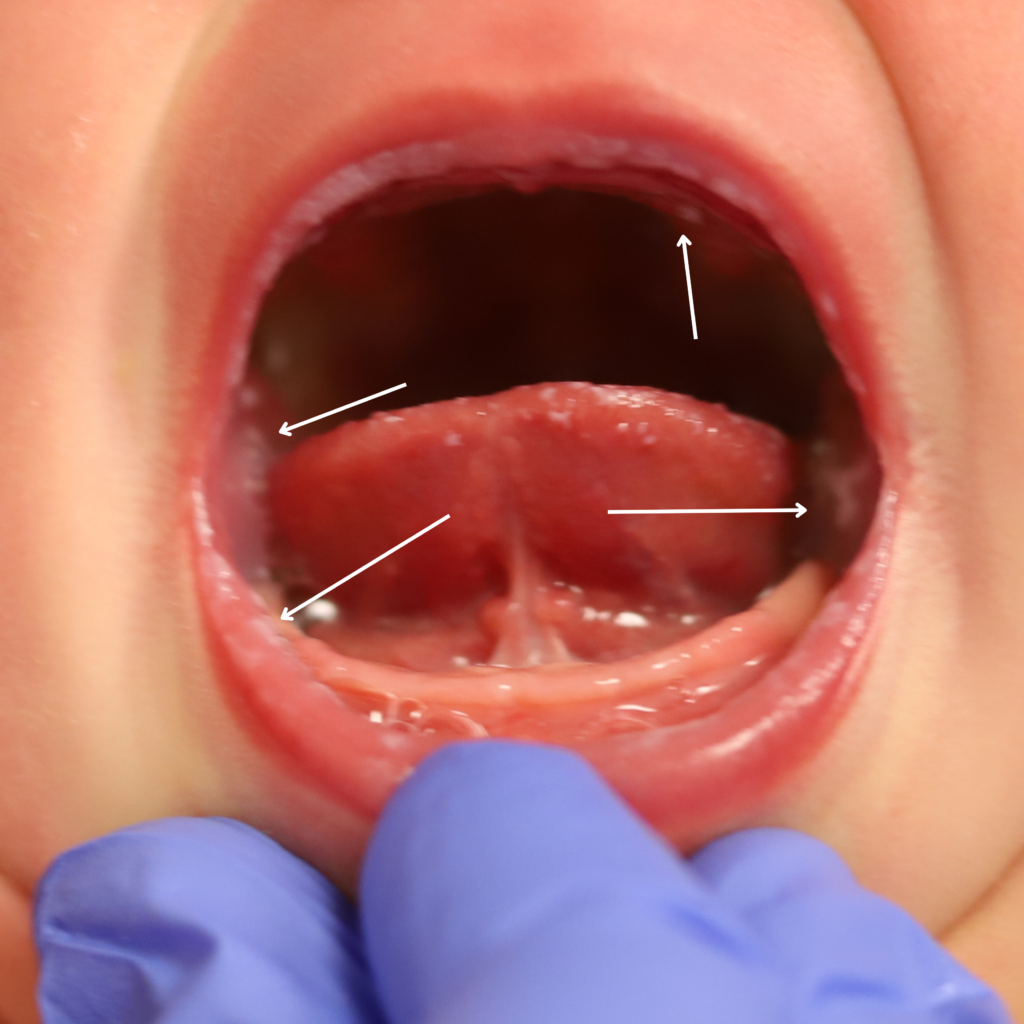

Ankyloglossia, or tongue tie, is the presence of a short, thick, or tight lingual frenulum (connective tissue underlying the tongue) that impairs sucking. This can occur as an “anterior” tongue tie (very tip of the tongue is attached to the lower gum), or a “posterior” tongue tie (further back on the floor of the mouth).

The interplay of baby’s mouth and mom’s breasts can impact lactation in different ways. Some babies with a restrictive frenulum can nurse without issue if mom’s nipples are elastic and she has ample milk production. Other infants with less restriction can struggle to feed if mom’s flow isn’t ideal for them. In some cases, infants also will have other oropharynx cavity variations, including high palates and generalized discoordinated sucking. These infants can benefit from occupational therapy exercises.

If you have any concerns about your infant’s oral cavity, seek evaluation from a knowledgeable pediatrician. Below are examples of an “anterior” frenulum that is attached from the end of the tongue to the gum line. These are generally addressed in the hospital or birth center before the baby goes home.